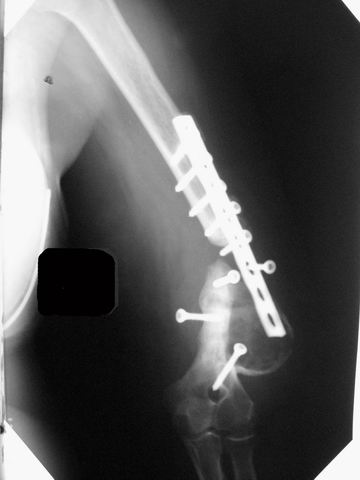

[Ortho] ложный сустав после остеосинтеза плеча

Уважаемые коллеги! Обратилась женщина 38 лет, соматически здорова, ORIF наружным доступом в 2005 году (к сожалению снимки пока не нашли), перелом типа В1. После остеосинтеза никуда не обращалась. Летом прошлого года (через 2 года после операции) во время перетаскивания стиральной машины появились боли в оперированном плече, но пришла лишь сейчас. Клинически: варусная деформация, патологическая подвижность, объем движений в локтевом суставе почти полный, неврологических расстройств нет, признаков инфекции нет. Коллеги, как вы думаете, возможно ли срастить данный неоартроз? Микрохирургия  недоступна. Честно говоря, не встречаясь с такими последствиями никогда ранее, надеюсь на помощь "коллективного разума".

Имя     : плечо AP.jpg